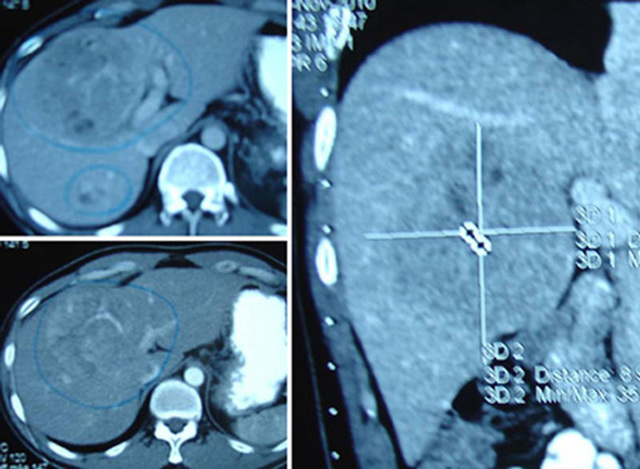

Нужно проверять печень. Обследоваться на вирусные гепатиты В и С. ИФА крови на ЦМВ и ВЭБ. Сделать УЗИ внутренних органов , а лучше КТ брюшной полости с контрастом. Что то дополнительно уже на очной консультации гастроэнтеролога или инфекциониста.